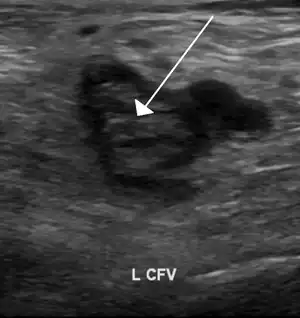

Deep vein thrombosis of the common femoral vein, seen with the probe in a transversal position. | |

Unlike arterial ultrasonography, venous ultrasonography is carried out with the probe in a transversal position, (perpendicular to the vein axis), displaying cross-sections of the veins.[4] All collateral veins are better detected this way, including perforator veins, but of most importance is the detection of venous thrombosis. The most reliable sign of thrombosis (even when a good image and color is present) is the absence of compressibility - A vein cannot be compressed when the blood is in a solid state, as with a thrombus, in the same way that a rubber pipe cannot be compressed if the water inside is frozen.[5] However, if the probe is parallel to the vein axis, when the examiner compresses it, the probe can slide to the right or to the left giving a false negative for thrombosis as the probe has moved away and the vein will not then be evident. Nevertheless, when the examiner needs to show the head thrombus in a printout, the probe will be presented parallel to the vein axis.[4]